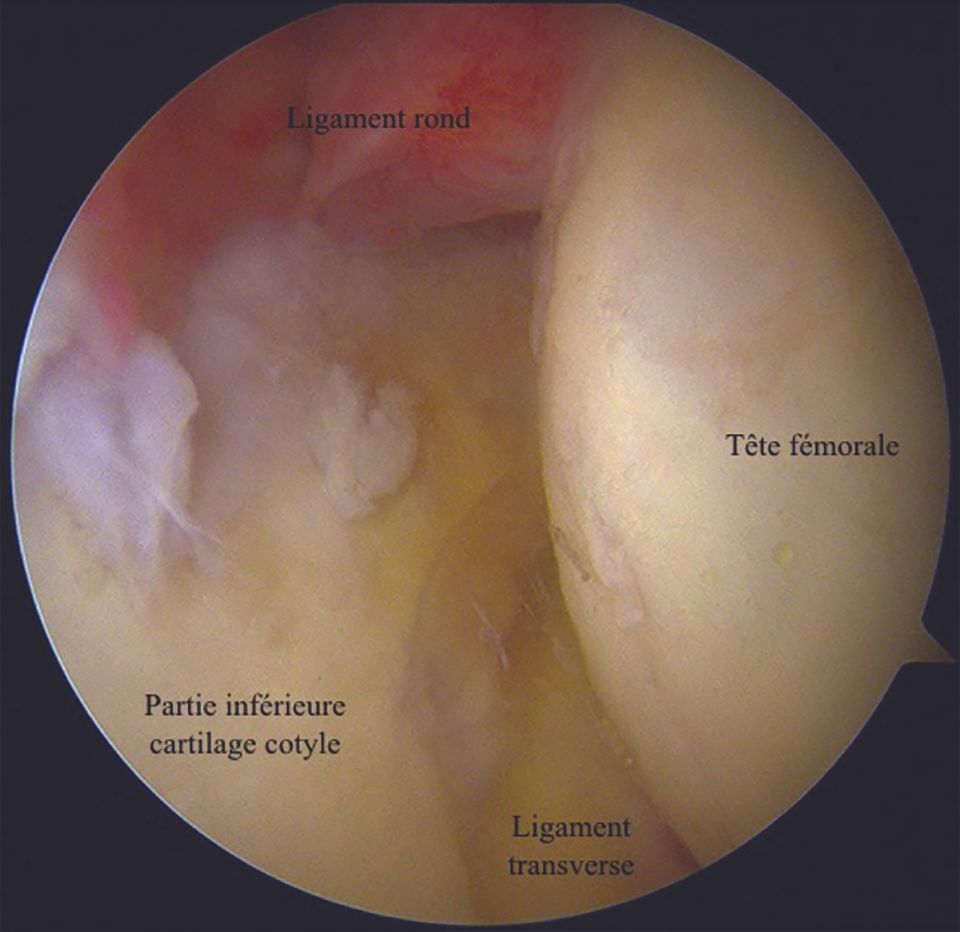

5. Posteroinferior view

This view allows the exploration of the inferior cartilaginous part of the acetabulum, the transverse ligament and its junction with the posterior portion of the labrum, and a part of the femoral head (Fig. 11).